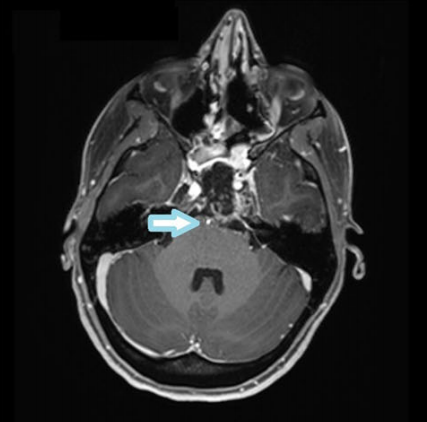

术后MRI显示近全肿瘤切除(残留部分位于海绵窦水平)和血管通畅(箭头指示)。